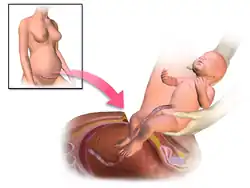

Nacimiento o expulsión

También llamado período expulsivo, termina con el nacimiento del bebé. Es el paso del recién nacido a través del canal del parto, desde el útero hasta el exterior, gracias a las contracciones involuntarias uterinas y a poderosas contracciones abdominales o pujos maternos. En el período expulsivo o segundo período distinguimos dos fases: la fase temprana no expulsiva, en la que la dilatación es completa, y no existe deseo de pujar ya que la presentación fetal no ha descendido y la fase avanzada expulsiva, en la que al llegar la parte fetal al suelo de la pelvis, se produce deseo de pujo materno. Es deseable no forzar los pujos hasta que la madre sienta esta sensación, para no interferir con el normal desarrollo del parto.